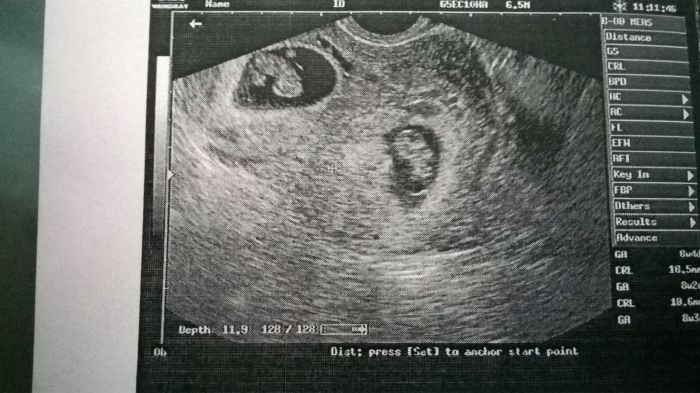

když mi dělala ultrazvuk, tak nevěřila vlastním očím, mám tam dvě miminka

když jsem to viděla, tak se ptám: a jsou obě živý??

takže syndrom mizejícího dvojčete nebyla správná diagnóza

prý ještě nemusel být vidět v 6 týdnu, když jsem byla na pohotovosti, protože ten jeden je vidět hůř, ale je tam, srdíčko mají obě, odpovídají stáří 8+4 a vypadají krásně živě

přikládám fotečku